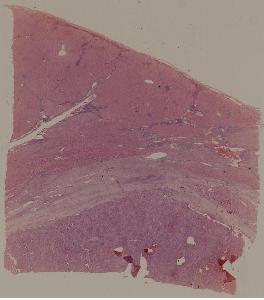

69.肝细胞性肝癌